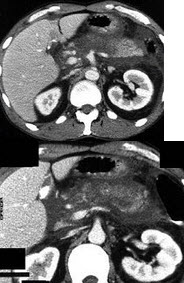

女,50岁,中上腹疼痛,消瘦乏力,影像检查如下图,最佳的诊断是( )

A:慢性胰腺炎

B:急性胰腺炎

C:胰腺癌并腹膜后淋巴结转移

D:胰岛素瘤

E:腹膜后淋巴瘤